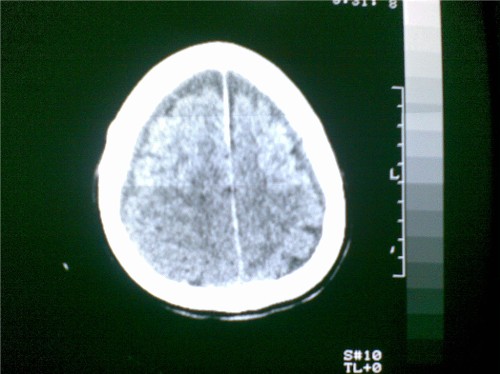

标题: CT28096:男,75岁,外伤10天后,现在恶心、呕吐。是硬膜下积 [打印本页]

硬膜下积液、右侧基底节、左侧放射冠腔梗。

硬膜下积液、多发性腔梗。

1)双侧额颞顶部硬膜下积液;建议必要时复查。2)多发性腔隙性脑梗塞。